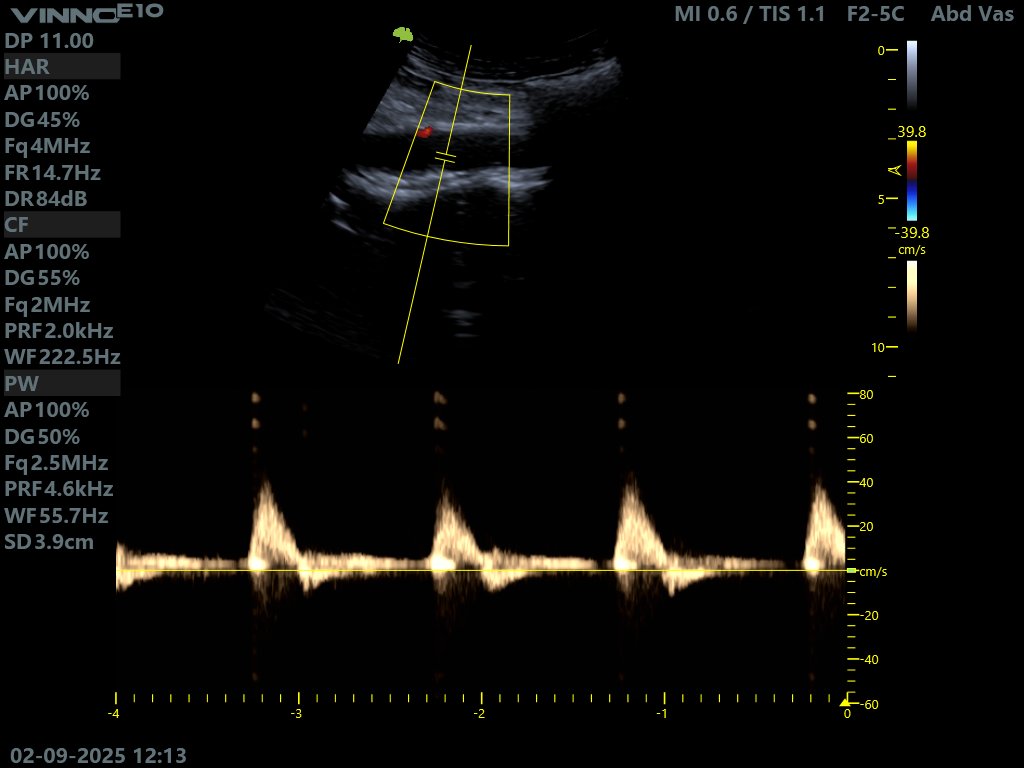

@tayfou La fémorale superficielle a un flux triphasique normalement, en absence de sténoses ou d'amortissement.

Le flux biphasique est celui de la fémorale profonde.

Belle icono mon frère

@kaddourkardio

Je sais que c'est au niveau de la female